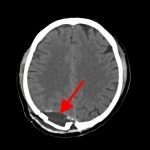

断層撮影

手術前1

手術前2